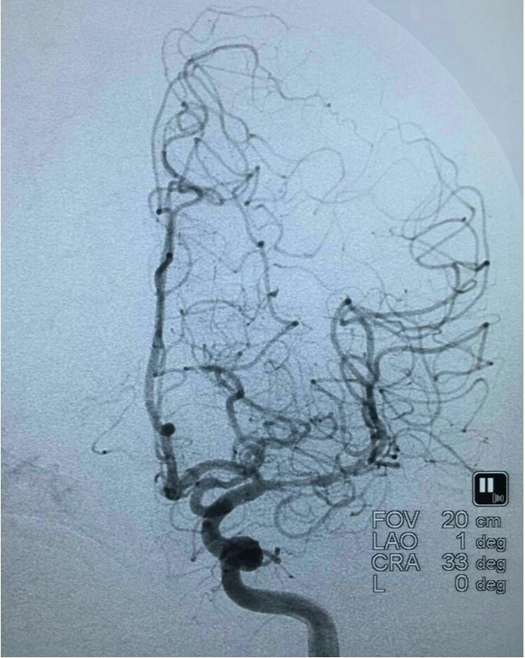

支架(Solitaire 4.0*20)到位尚未打开: